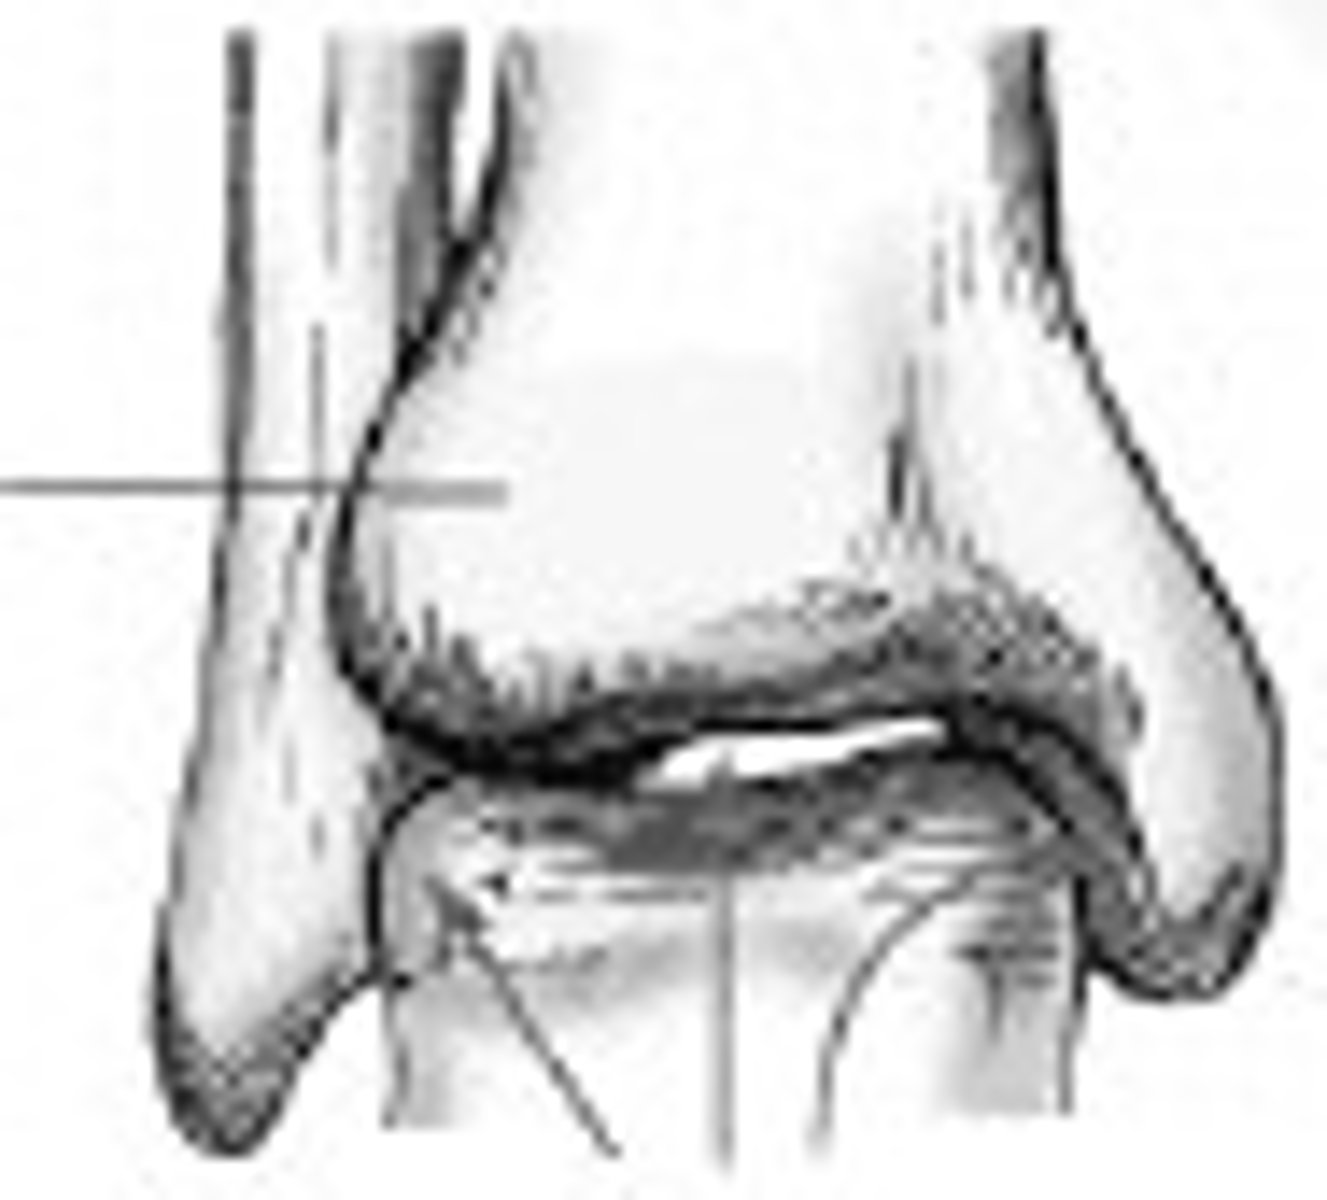

mortise joint

c

tibial plafond

medial malleolus